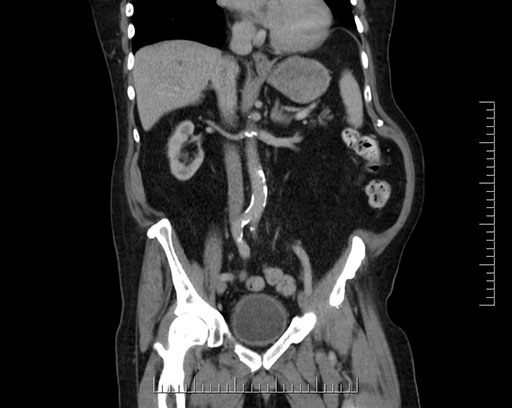

Imaging Analysis

Look through the patient's CT scan to identify any areas of concern for the necessary procedure.

Based on your CT findings, which issue(s) would give reason for "planned slowing down moment(s)" in this case?

Considering a standard Whipple procedure, what step(s) of the operation would you do differently in this case?